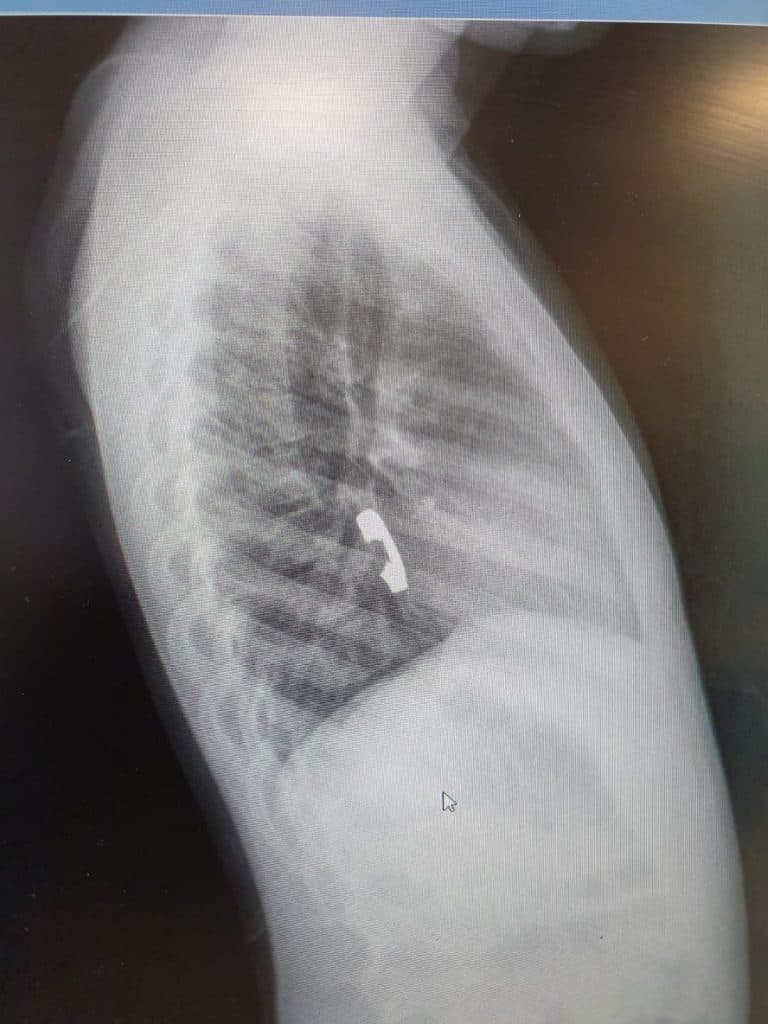

לאחר שחשה כאבים באיזור החזה היא הובהלה לבית החולים, שם בוצעו לה צילומים שהראו כי הטבעת נתקעה בושט. בעקבות האבחנה הוחלט לבצע פעולת גסטרוסקופיה בהרדמה מלאה להוצאת הטבעת.

בשל היותה של הטבעת חתוכה, נדרשה תשומת לב גדולה יותר ורמת דיוק גבוהה, על מנת שלא לפצוע את הנתיב בו הוצאה הטבעת החוצה.

מי שביצע בהצלחה את הפעולה בהרדמה כללית ובחדר הניתוח, היה רופא גסטרו ילדים במרכז הרפואי זיו, ד"ר ביאן הינו, בעזרת אחראית מכון גסטרו האחות שרי טרבלסי וצוות חדר הניתוח. שירה בת ה-6 אושפזה להשגחה באותו הלילה ושחררה למחרת בריאה ושלמה.

ד"ר ביאן הינו אמר לאחר האירוע, "ילדים בולעים גופים זרים שונים, אבל יש כמה שדורשים התייחסות מיוחדת והוצאה אנדוסקופית מיידית כשהם בטווח השגה. במקרה הזה, הילדה בת ה-6 בלעה טבעת שנתקעה בושט ולכן נדרשה הוצאה אנדוסקופית בהרדמה כללית בחדר. על ההורים והמטפלים מוטלת החובה לשמור היטב על ילדיהם מסכנות אלו".